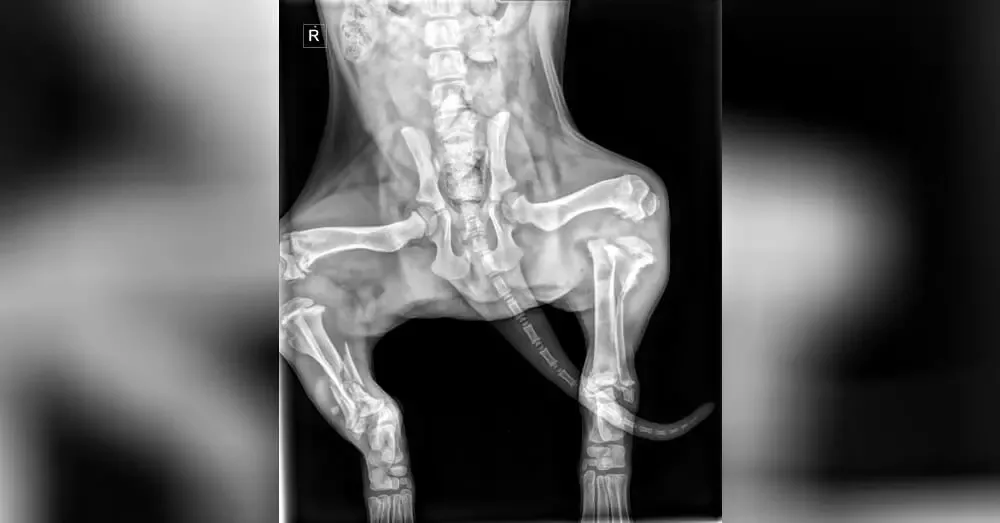

X-rays revealed horrific damage to both of Buddy’s back legs.

Both of Buddy’s tibias were fractured in what the orthopedic surgeon described as the worst broken bones he’d ever seen in a puppy.

They placed external hardware called an “external fixator” on Buddy’s left leg, and surgically implanted two plates and five pins in Buddy’s right leg.